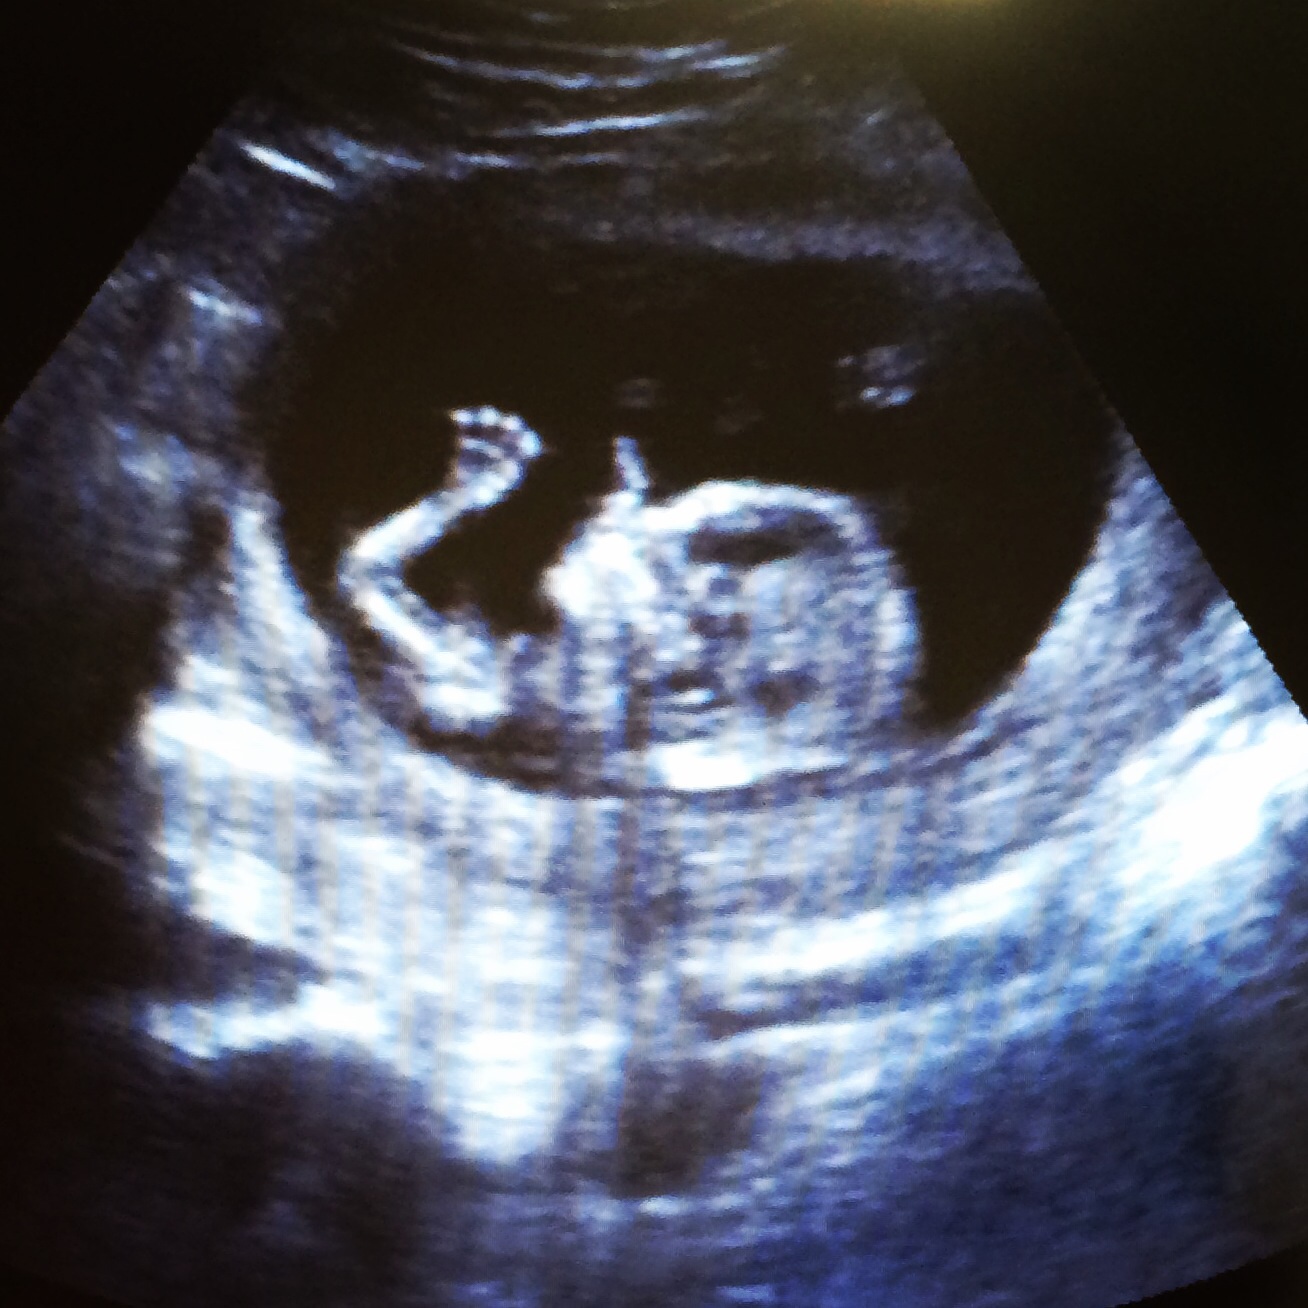

Yesterday I went in for the 12 week scan, including NT screening. Here's the little one. They also showed me in 3-d & the baby was holding onto the placenta.